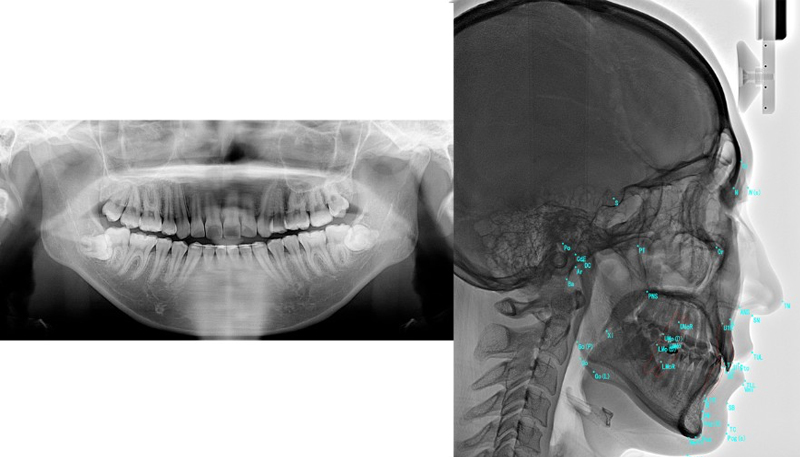

②精密検査

より正確な診断・治療計画のために、必要な検査をすべて院内で行います。内容は以下の通りです。

検査内容

・歯科用CT撮影

・頭部エックス線規格写真

(セファログラム)

・口腔内スキャナー(iTero)による3Dスキャン

・顔貌・口腔内写真撮影

これにより、歯や骨格の状態を立体的に把握できます。

次の診断は最短で3日後から対応可能ですので、スピーディーに治療を開始できます。

費用:44,000円(税込)